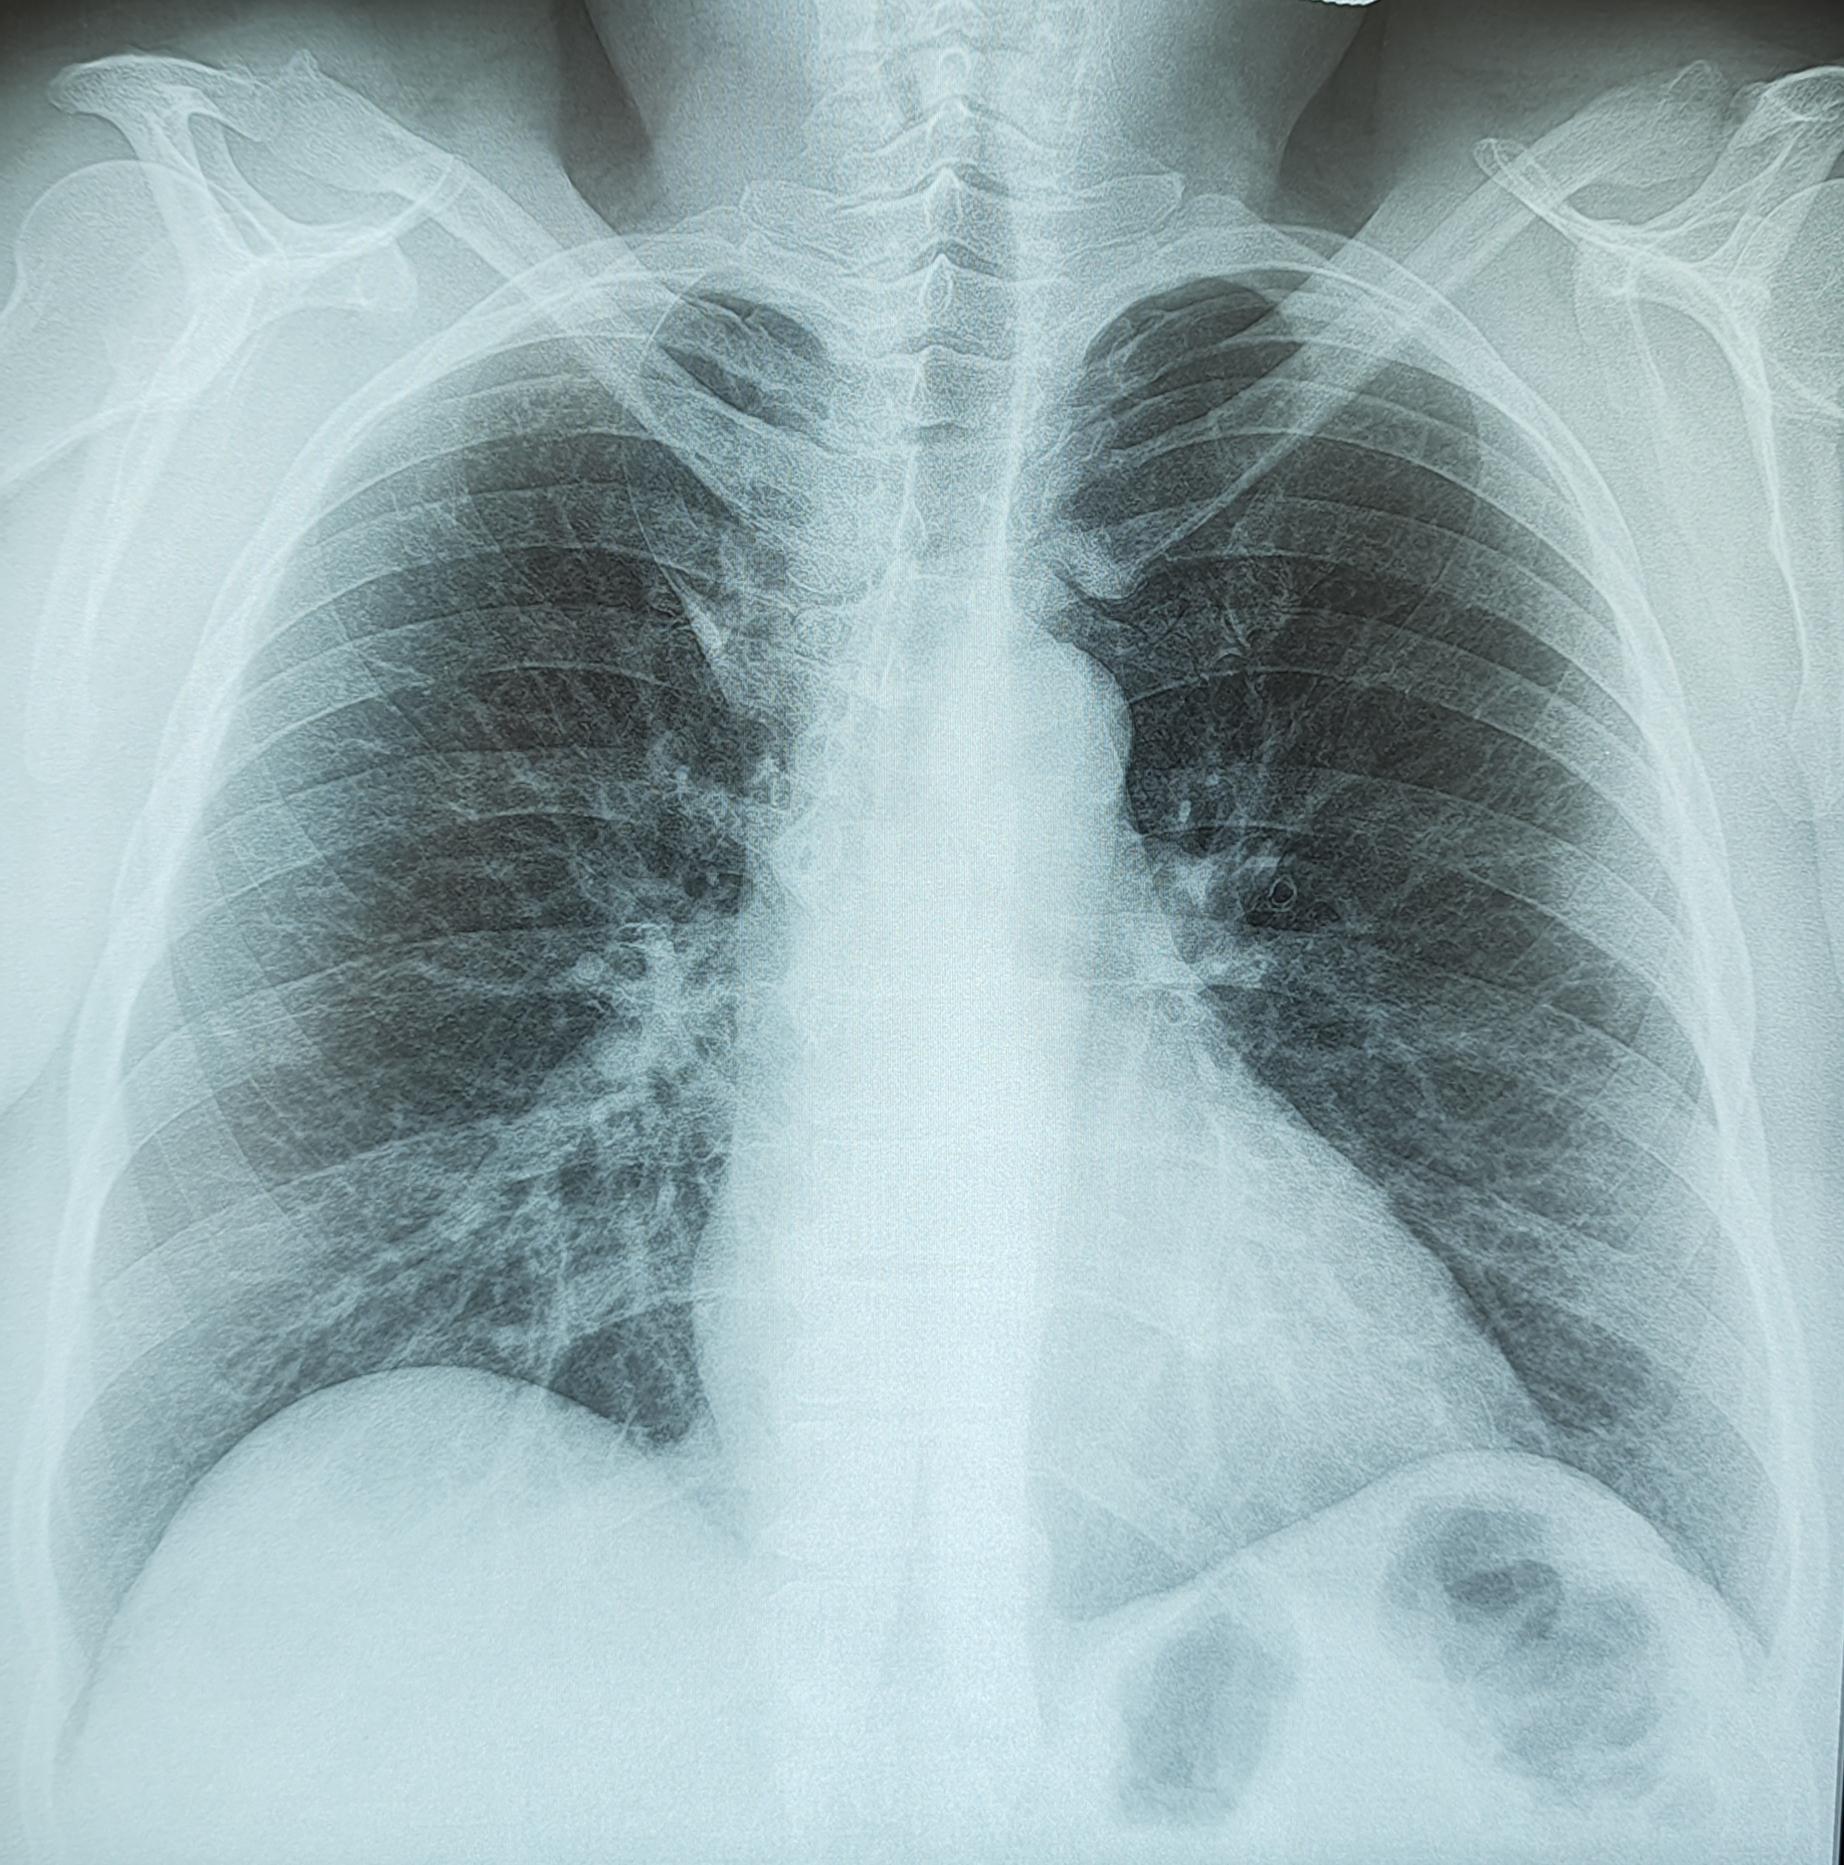

Справа по парастернальной линии, чаще на уровне 1-го межреберья (иногда на уровне хрящевой части 1 или 2-го ребер) определяется небольшая в форме вытянутой капли тень (от 0,3 до 0,8 мм ширины и от 0,6 до 2,5 мм длины) с четкими контурами. Эта «капля», заостряясь кверху, переходит в нежную (волосяную) линейную тень добавочной междолевой щели; она направлена кверху и дугообразно изгибается выпуклостью кнаружи.

Порок развития протекает бессимптомно. Его диагностируют на рентгенограммах, флюорограммах в прямой/задней проекциях.